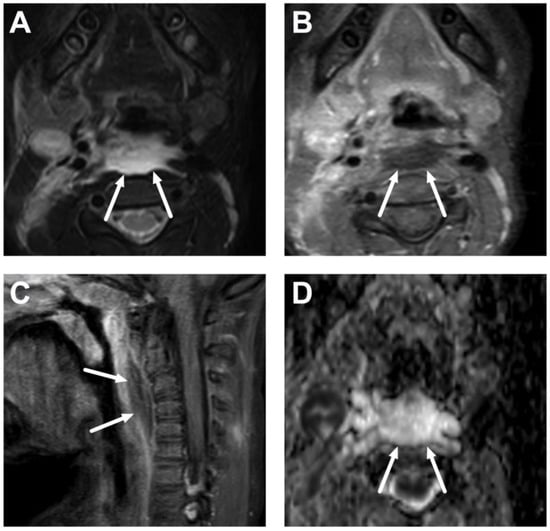

6.1. Mediastinitis

6.2. Venous Thrombosis